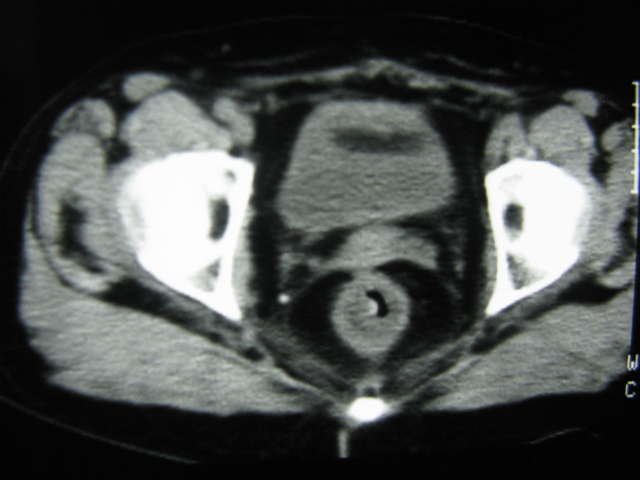

患者,女,64岁,2002年诊断为宫颈癌,当时只做过放,化疗。现在诊断:(1)宫颈癌。(2)直肠癌。请同道们讨论,探讨。另外肠壁为啥密度这么高,ct值约112hu。患者没有做过增强和造影。

高密度的不是肠管影,是肠管内的粪便影

患者直肠病变,排便不畅,粪便硬结造成,更高密度如钡灌肠者都可出现

患者是否长期服用抗癌药物?应与服用药物有关!

是否与放、化疗有关?

我也碰到过几例,最离奇的一例是全结肠呈造影样高密度,患者直肠癌(首次发现),以往没有吃药,只有约半年时间长的胃纳差,排便不畅(据患者说每次大便只能拉出少许黄水)

不一定有意义,可清洁灌肠后复查